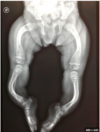

A neonate born with clubbed feet dies shortly after birth due to severe respiratory distress. His mother had not sought antenatal care. Post-mortem shows pulmonary hypoplasia.

Which of the following clinical features would most likely also be present?

Bilateral renal agenesis and oligohydramnios